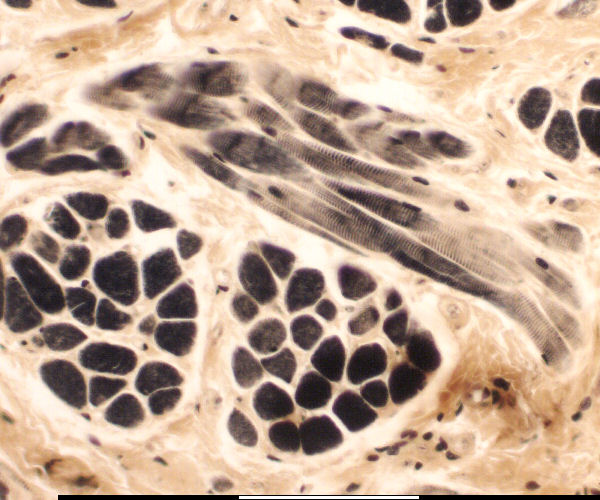

Lengte en skuinssnit van spiervesels

Cross and diagonal section of muscle fibers

Skuinssnit /

Diagonal section

Dwarssnit /

Cross section

Perimesium /

Perimysium

Kerne /

Nuclei

Endomesium /

Endomysium